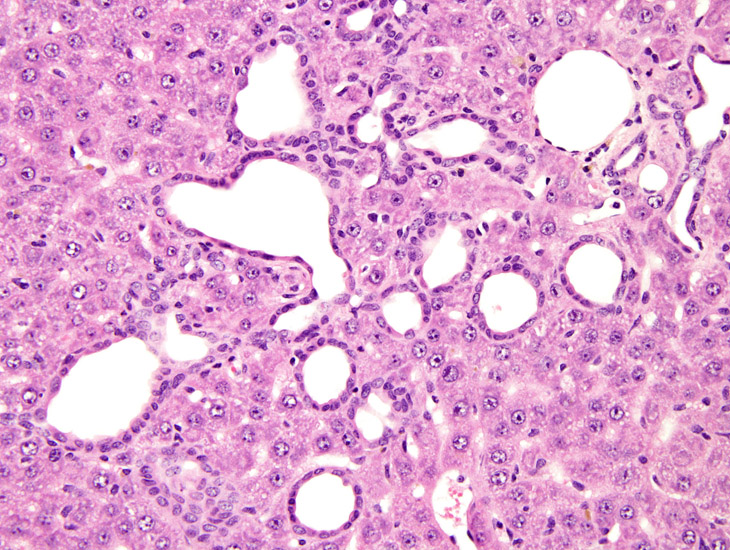

Higher magnification showing low cuboidal to flattened biliary epithelium forming irregularly shaped bile ducts.